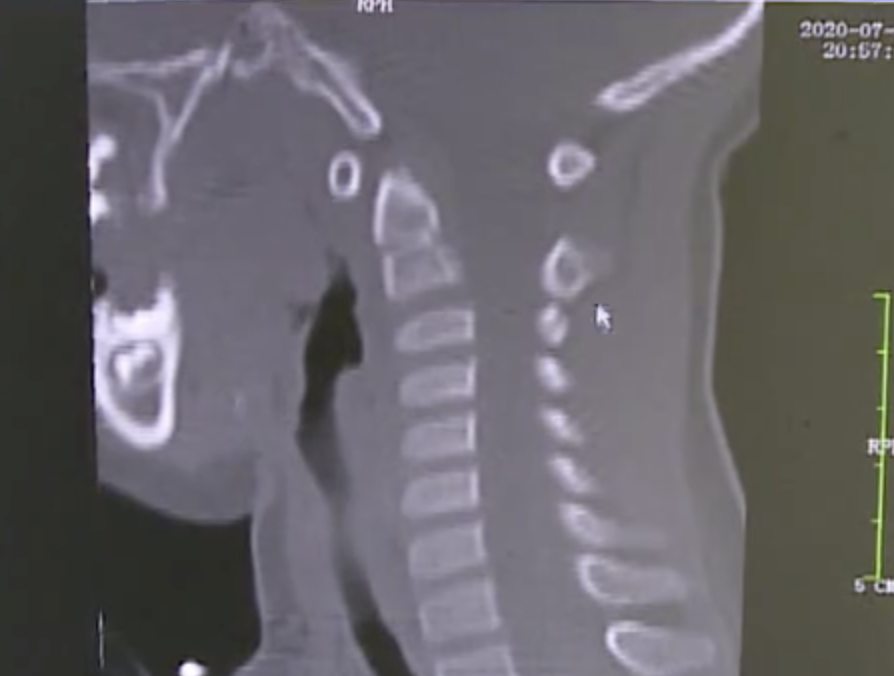

从女童的片子来看

她的颈椎已经变形了

“正常来说我们的颈椎是有S曲线的”